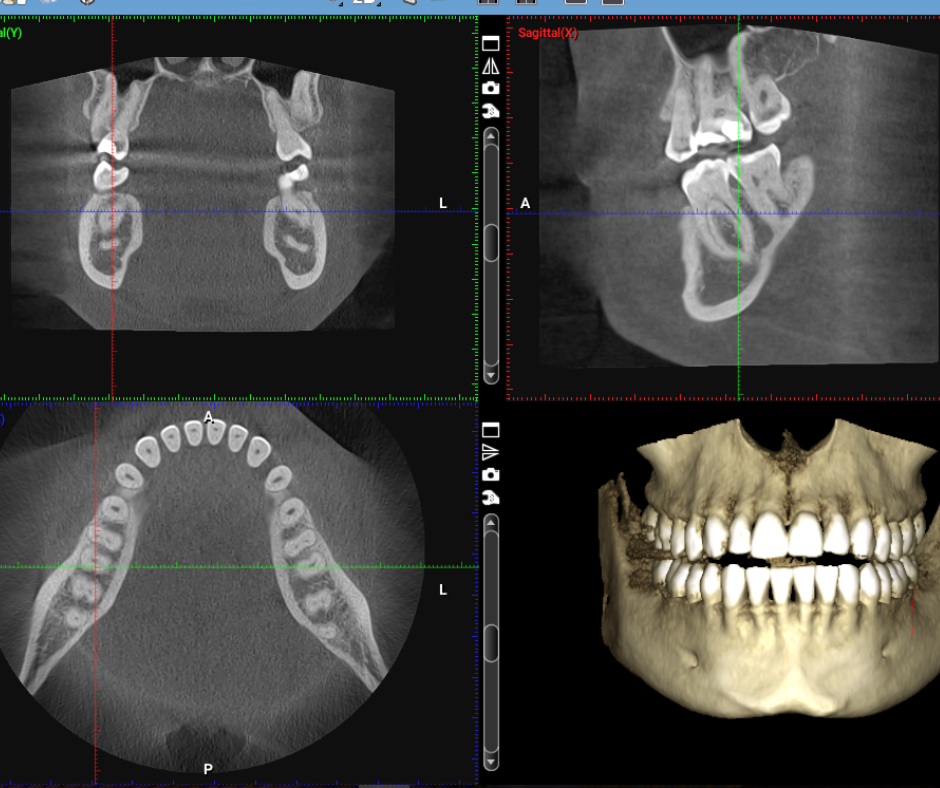

A full-arch dental implant restoration is a life-changing solution for patients who are missing most or all of their teeth, offering a stable, fixed alternative to dentures. Using as few as four to six strategically placed implants, we support an entire upper or lower arch of natural-looking teeth that stay securely in place—no slipping, adhesives, or nightly removal. At National Dental Implant Center of Hauppauge, we use advanced CBCT imaging, digital planning, and guided surgical techniques to ensure each implant is positioned with exceptional accuracy for long-term success. This modern full-arch approach restores full chewing ability, enhances facial support, and delivers a confident, functional smile that looks and feels completely natural.

Beyond aesthetics, full-arch implant restorations are designed to protect long-term oral health and facial structure. When multiple teeth are missing, the jawbone naturally shrinks over time, leading to a sunken appearance and changes in bite alignment. By placing implants that integrate directly with the bone, we restore essential support, stimulate bone retention, and create a strong foundation for a long-lasting smile. At National Dental Implant Center of Hauppauge, our digitally guided workflow ensures every step — from implant placement to final bridge design — is executed with exceptional precision. The result is a durable, functional, and natural-looking full-arch restoration that allows patients to eat, speak, and live with complete confidence.